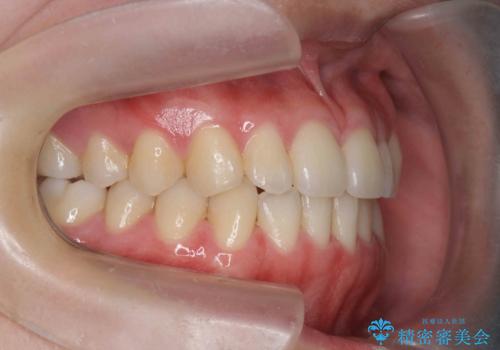

ガタつきの改善 マウスピース矯正治療

- 歯のがたつきの改善を求めて、矯正治療を希望され来院されました。

少量の歯のディスキング、歯列弓拡大、アタッチメントを装着することで審美的な歯列へとマウスピース矯正インビザラインを用いて治療を行います。

マウスピース矯正は装着時間の遵守が非常に大切ですが、しっかりと20時間/日以上の装着を守っていただいたおかげで良好な治療結果を得ることができました。